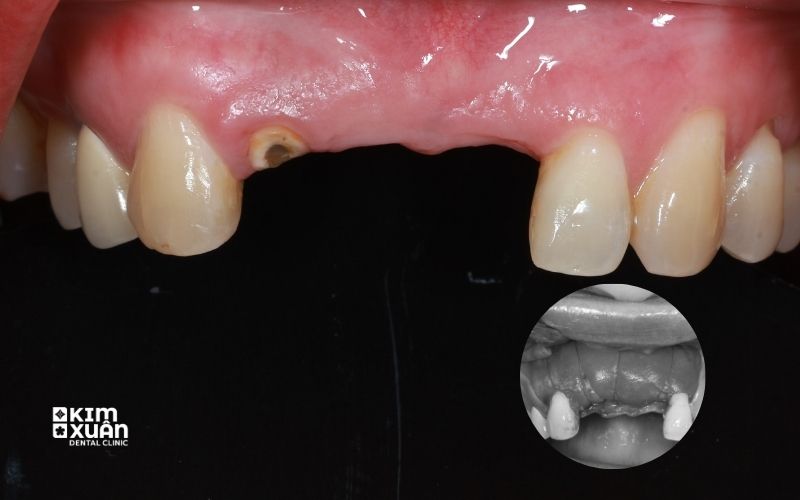

Sau khi mất răng, xương hàm sẽ tiêu dần theo thời gian do không còn lực nhai kích thích. Đây là quá trình tự nhiên nhưng nếu kéo dài, xương hàm có thể suy giảm nghiêm trọng và không đủ điều kiện để cấy ghép Implant.

Cụ thể, tình trạng tiêu xương hàm có thể gây ra:

-

Giảm chiều cao và độ dày xương hàm

Mật độ xương suy giảm, xương trở nên yếu và xốp

Không đủ nền xương để đặt trụ Implant an toàn

Khi đó, nếu cố gắng cấy Implant trực tiếp, trụ Implant có nguy cơ lung lay, không tích hợp hoặc bị đào thải sau một thời gian ngắn.

Ghép xương răng implant giúp tái tạo lại nền xương hàm vững chắc, tạo điều kiện để trụ Implant tích hợp ổn định và duy trì khả năng ăn nhai lâu dài.